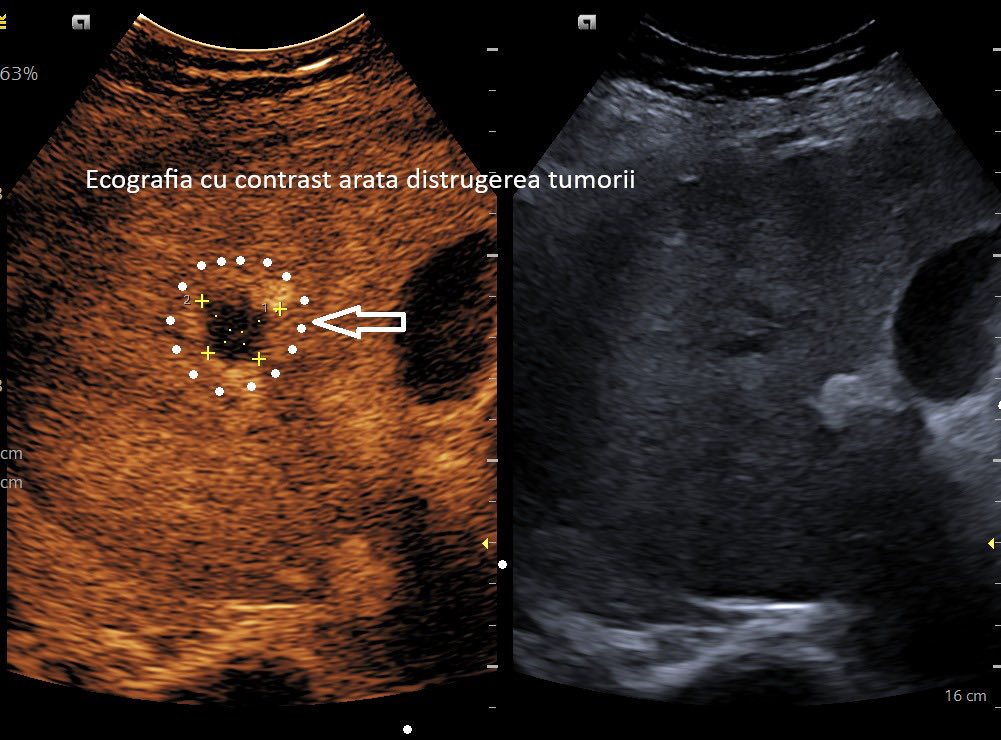

Potrivit sursei, la doar o lună după intervenție, investigațiile imagistice au confirmat distrugerea completă a tumorii.